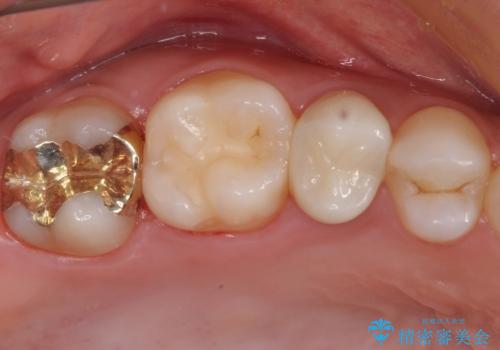

どちらの歯も痛みなどの症状はなく、治療後も異常所見なく経過をたどっています。

上顎大臼歯は向かい合った人から見えることはほとんどないため、切削量が少なく、適合の良いゴールドインレーが大変おすすめとなります。